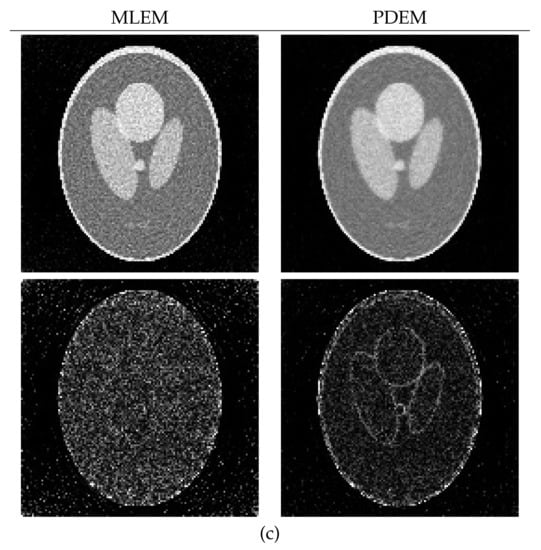

4.1. Reconstruction Using Numerical Phantom

4.2. Reconstruction Using Physical Phantom